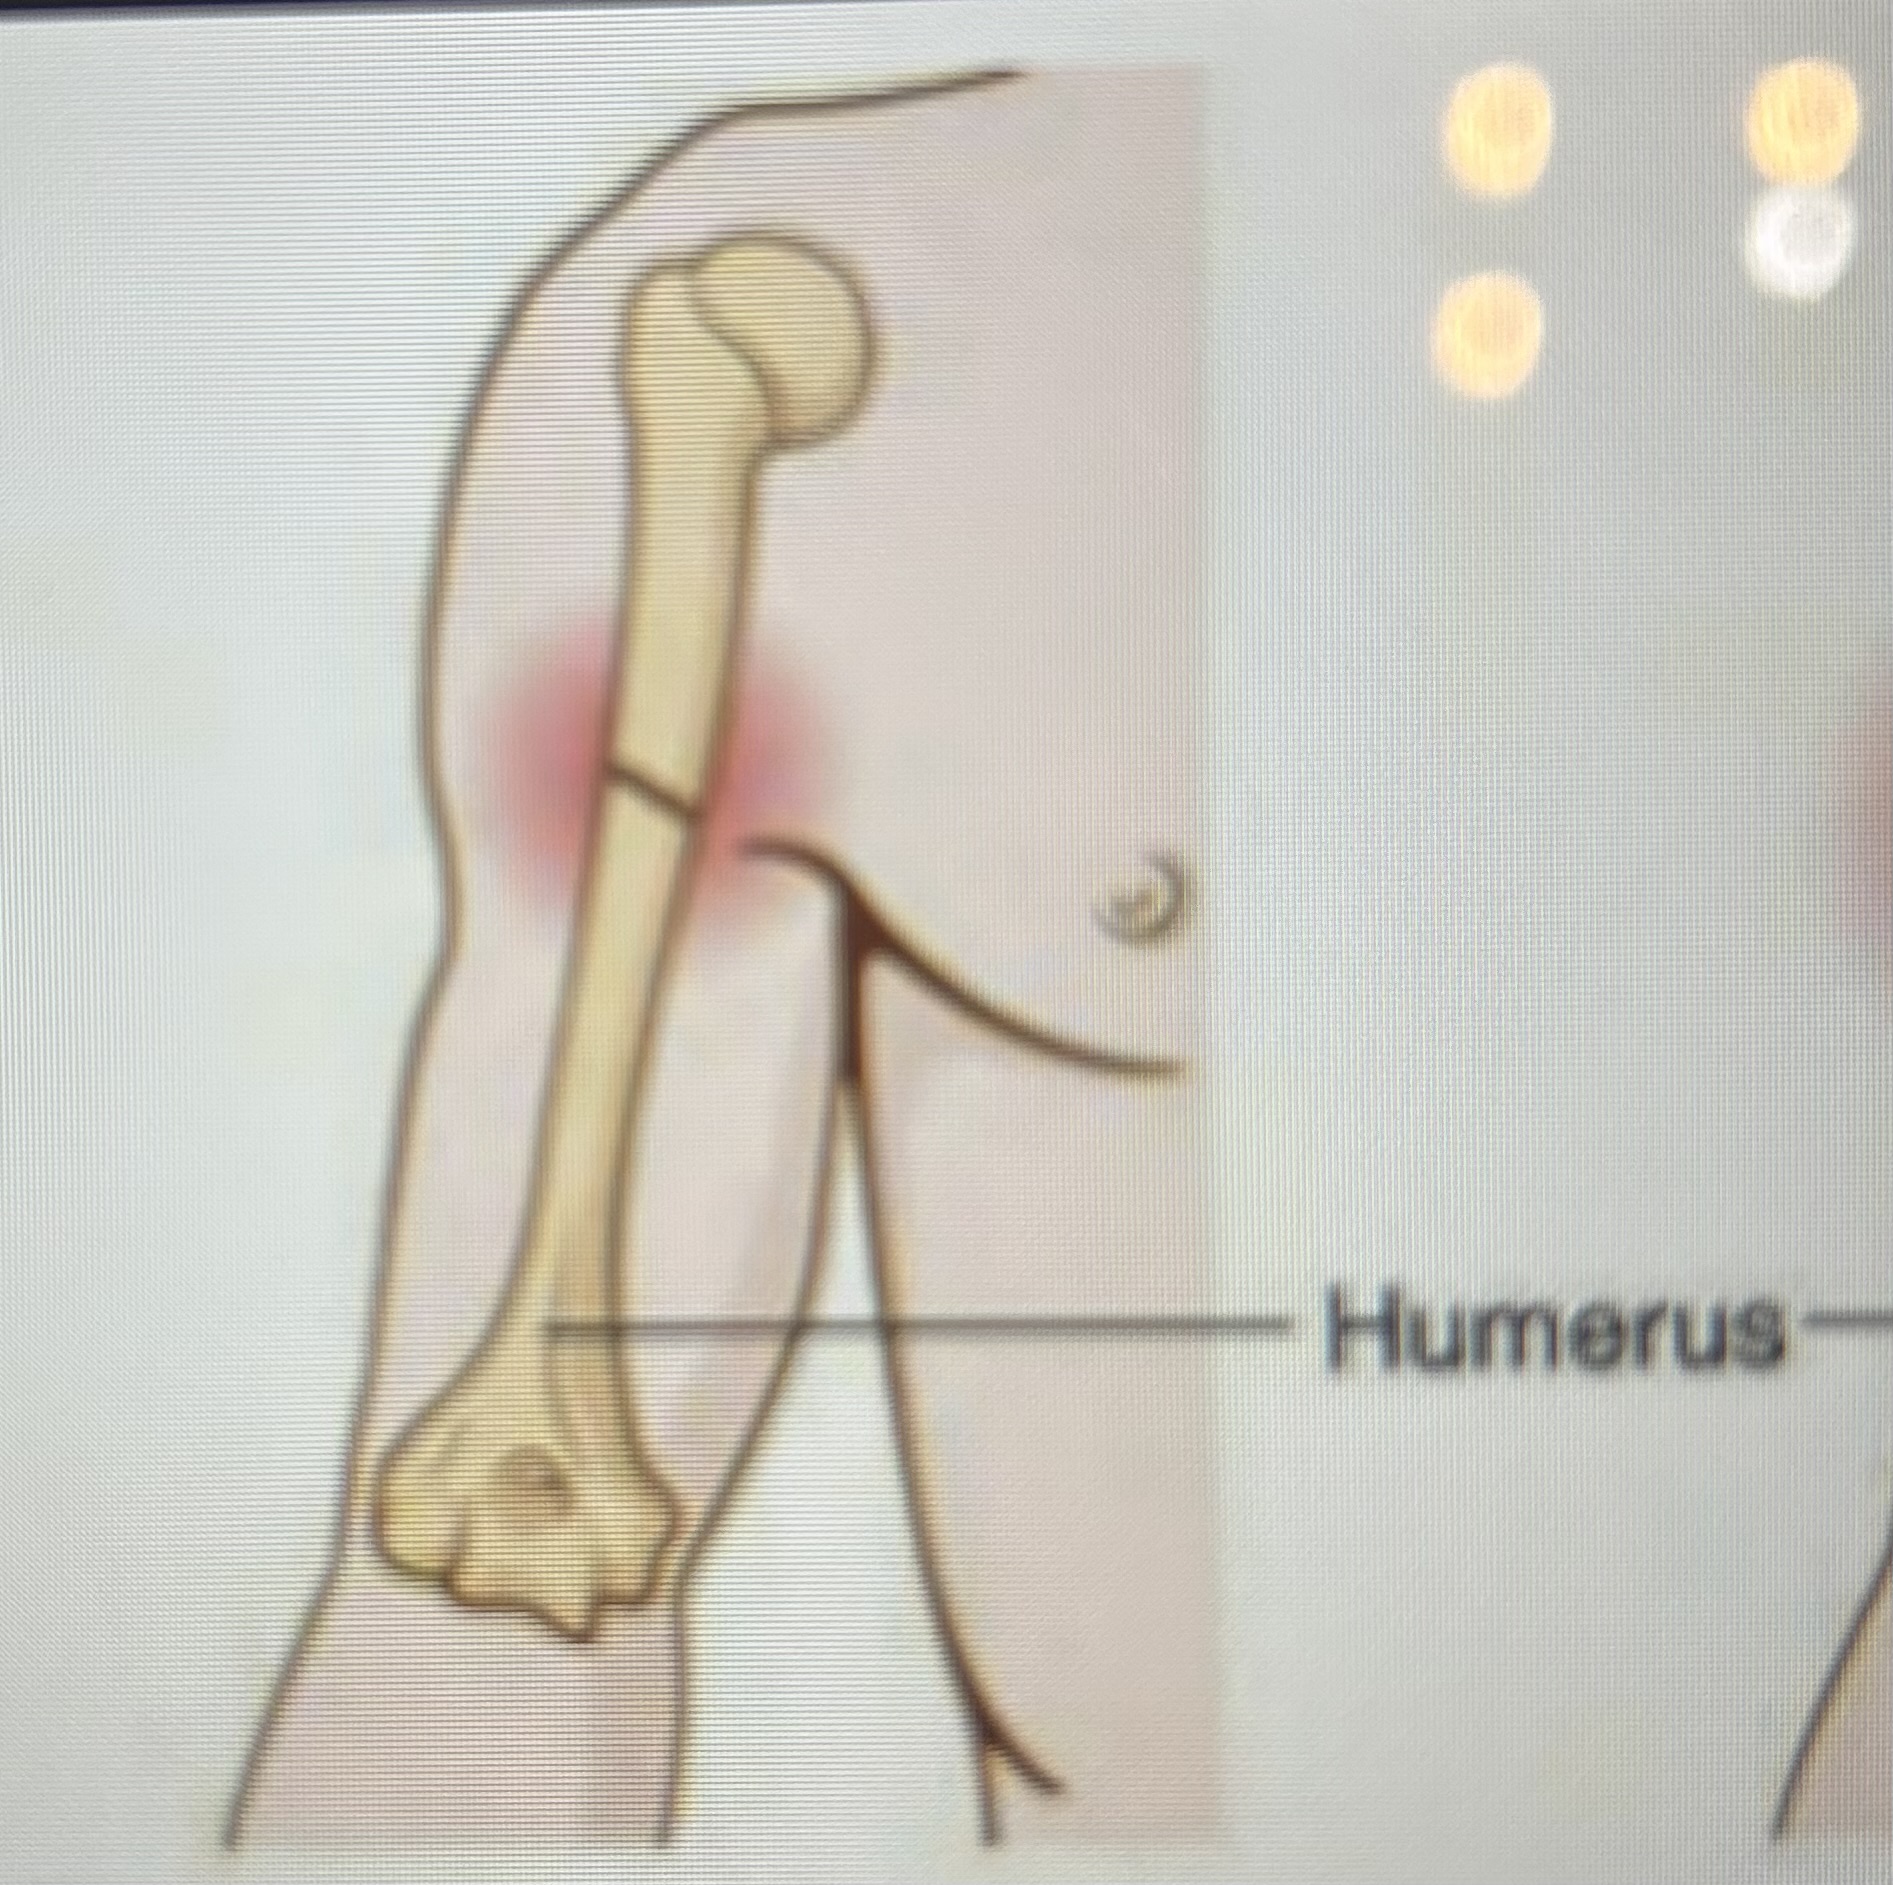

What type of fracture is this?

Simple/closed fracture

What type of fracture is this?

Compound/open fracture